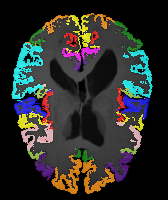

Image Manual Seg DA-1 Mono-21 DA-21 Mono-65 Refer to caption Refer to caption Refer to caption Refer to caption Refer to caption Refer to caption

Figure 2:  Examples of knee MRI registration (top) and brain MRI segmentation (bottom) results. Top: The first two columns are the moving image/segmentation and the target image/segmentation followed by the warped moving images (with deformation grids)/segmentations by different models. Bottom left to right: original image, manual segmentation, and predictions of various models. Mono-i𝑖i and DA-i𝑖i represent the mono- and DA models with i𝑖i manual segmentations respectively.

Brain results: Dice scores for segmentation and registration increase by about 2.6 and 3.5 respectively for the cortical structures of the brain MRIs.

Qualitative results: DA achieves more anatomically consistent registrations than the mono-networks on the knee (Fig. 2) and Brain MRI samples (see supplementary material).